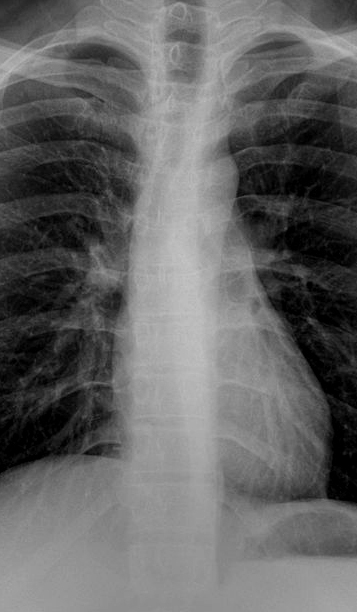

Index cardio-thoracique

: Index thoacique / coeur normalement est egale

de moindre 48 -50% et chez le nourisson cette index peut de

moindre 55% .

Les lignes de reflextion

mediastinale

| Lignes mediastinales |

| 1 Para-arterielle gauche-veine

sousclaviere |

| 2 Mediastinale posterieure |

| 3.Paraveineuse superieure droit |

| 4 Para azygos |

| 5 Mediastinale anterieure |

| 6 Para aortique |

| 7 .Paravertebrale droite et gauche |

| 8 Veine cave inferieure |

| 9 Para-oesophagienne ( bord droit

de oesophage) |

| 10.Para tracheale droite ( bord droit

trachee ) |